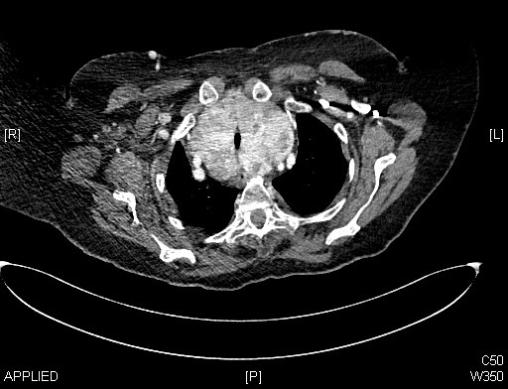

Scanner thoracique d’un goitre plongeant.

Extrait de : Conduite à tenir devant un goitre plongeant